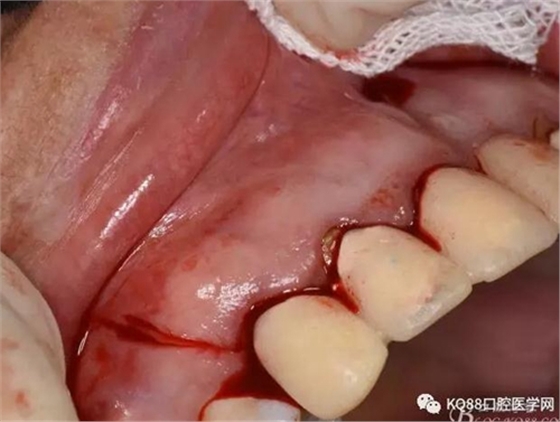

圖5.唇側(cè)局部浸潤麻醉

圖6.腭側(cè)浸潤麻醉

圖7. 分別在13的遠(yuǎn)中和11的近中做垂直切口加齦溝內(nèi)水平切口,形成梯形瓣

圖8.翻開梯形瓣